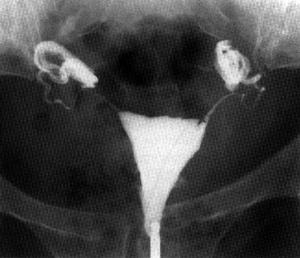

HYSTERO-SALPINGOGRAPHIE

(opacification de l'utérus et des trompes)